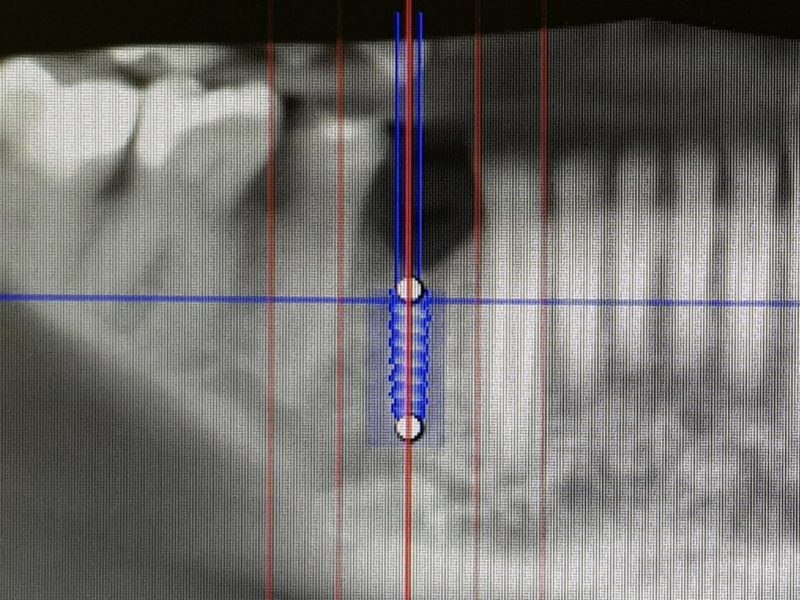

This case is presenting immediate implant placement in lower jaw in premolar region with lack of bone height and width. Patient had complicated extraction of root 44 which lead to greater bone loss. Implant placement was carefully planned with the help of 3D CBCT scan. Since there was lack of bone height towards mental canal, we planned to leave part of the implant not covered by bone and above crest line. Missing bone was augmented with the help of artificial bone regeneration material in combination with platelet rich fibrin creating “sticky bone”. Implant used in this case was 3P by B&B dental, and later we placed screw-retained metal-ceramic crown.